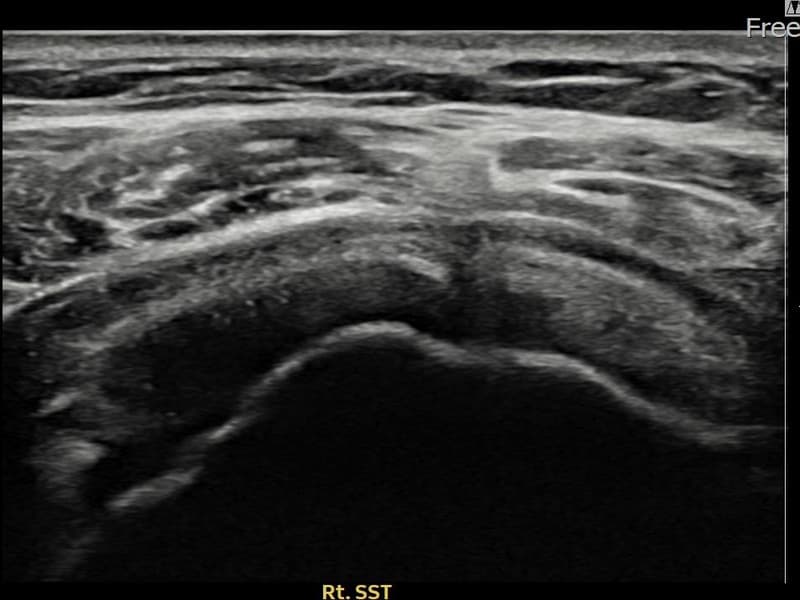

术前

术前超声确认右侧 冈上肌腱 关节面侧部分撕裂,右侧冈上肌腱回声不连续伴肌腱缺损(7mm × 3mm (肌腱厚度约30%缺损))。术后超声显示撕裂部位充满再生组织,肌腱连续性恢复,回声模式正常化。